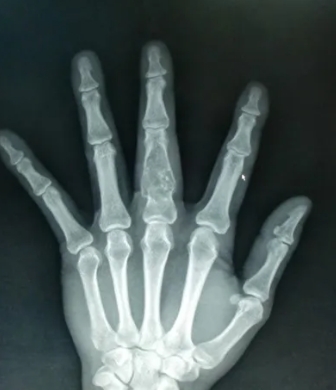

掌指骨常见肿瘤的影像学表现